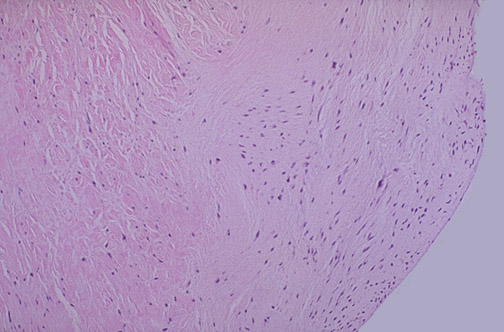

| There is plaque-like fibrous endocardial thickening at the right overlying the myocardium at the left. This may be seen in the right heart endocardium and valve leaflets with the rare carcinoid syndrome, as a consequence of secretion of bioactive substances such as serotonin (measured by its metabolite 5-hydroxy-indoleacetic acid, or 5-HIAA). This same pattern can appear in the left heart in patients taking the drug dexfenfluramine (part of the "phen-fen" combination for weight loss), which increases serotonergic activity. |